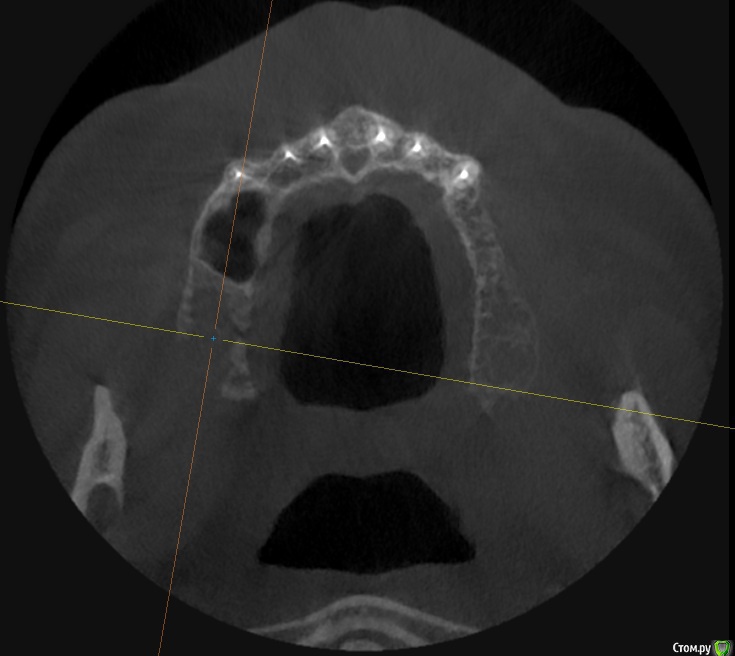

alboard Опубликовано 9 марта, 2017 Поделиться Опубликовано 9 марта, 2017 В области 16,17,18 дно отсутствует. Какая здесь может быть тактика? Ссылка на комментарий

Dok22 Опубликовано 9 марта, 2017 Поделиться Опубликовано 9 марта, 2017 В пазухе какое то образование. 1 Ссылка на комментарий

mr.Fog Опубликовано 9 марта, 2017 Поделиться Опубликовано 9 марта, 2017 Скорее всего это кальцифицированные останки радикулярной кисты. Ссылка на комментарий

Oscar Опубликовано 9 марта, 2017 Поделиться Опубликовано 9 марта, 2017 давно зубы удалены? Похоже на ретенционную кисту пазухи... Можно попробовать отслоить шнайдер снизу, если перфорация выход только "парашют"... Ссылка на комментарий

drpetrovich Опубликовано 13 марта, 2017 Поделиться Опубликовано 13 марта, 2017 Действительно по томограмме больше похоже на резидуальную кисту, т.е. при зондировании проваливаешься не в пазуху, а в полость кисты. Отделяемое было кстати? Вопрос про давность удаления актуален. Ссылка на комментарий